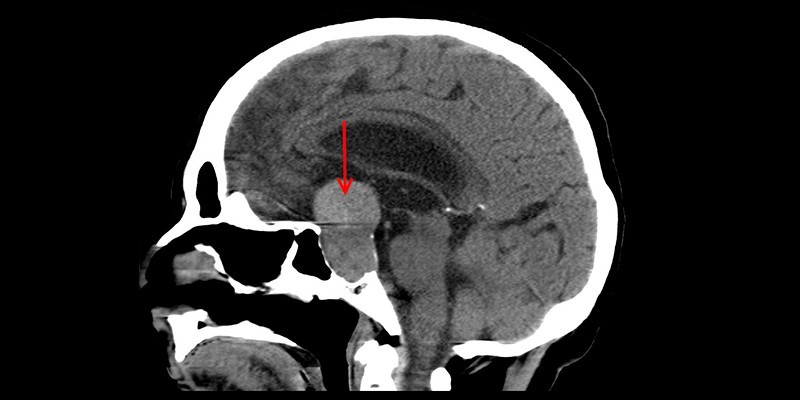

МРТ

Магнитно-резонансная томография определяет размер, локализацию опухоли, ее воздействие на окружающие ткани, наличие кровоизлияний, гиперинтенсивных кист.

Это безопасный и информативный метод исследования, не воздействующий отрицательно на зоны головного мозга. Особенностью МРТ опухоли гипофиза является то, что по показателям не только определяется наличие и характер аденомы, но и устанавливается, какие системы организма от нее могут пострадать.

Это врач видит по месторасположению новообразования.

С помощью магнитной томографии определяются все виды аденом: микроаденомы, макроаденомы, гигантские опухоли. Как правило, МРТ проводится без применения контрастирования, поскольку новообразование легко визуализировать в любых проекциях и срезах, в плоском и объемном изображении. При больших аденомах или для подтверждения онкологического диагноза применяют внутривенное введение контраста.

При анализе результатов МРТ размеры гипофиза в норме у женщин и мужчин составляют 10-17 мм по ширине, 3-8 мм по высоте. Магнитная томография не имеет возрастных ограничений. Недостатками диагностики являются: длительность процедуры и высокая стоимость. Противопоказания к проведению МРТ: